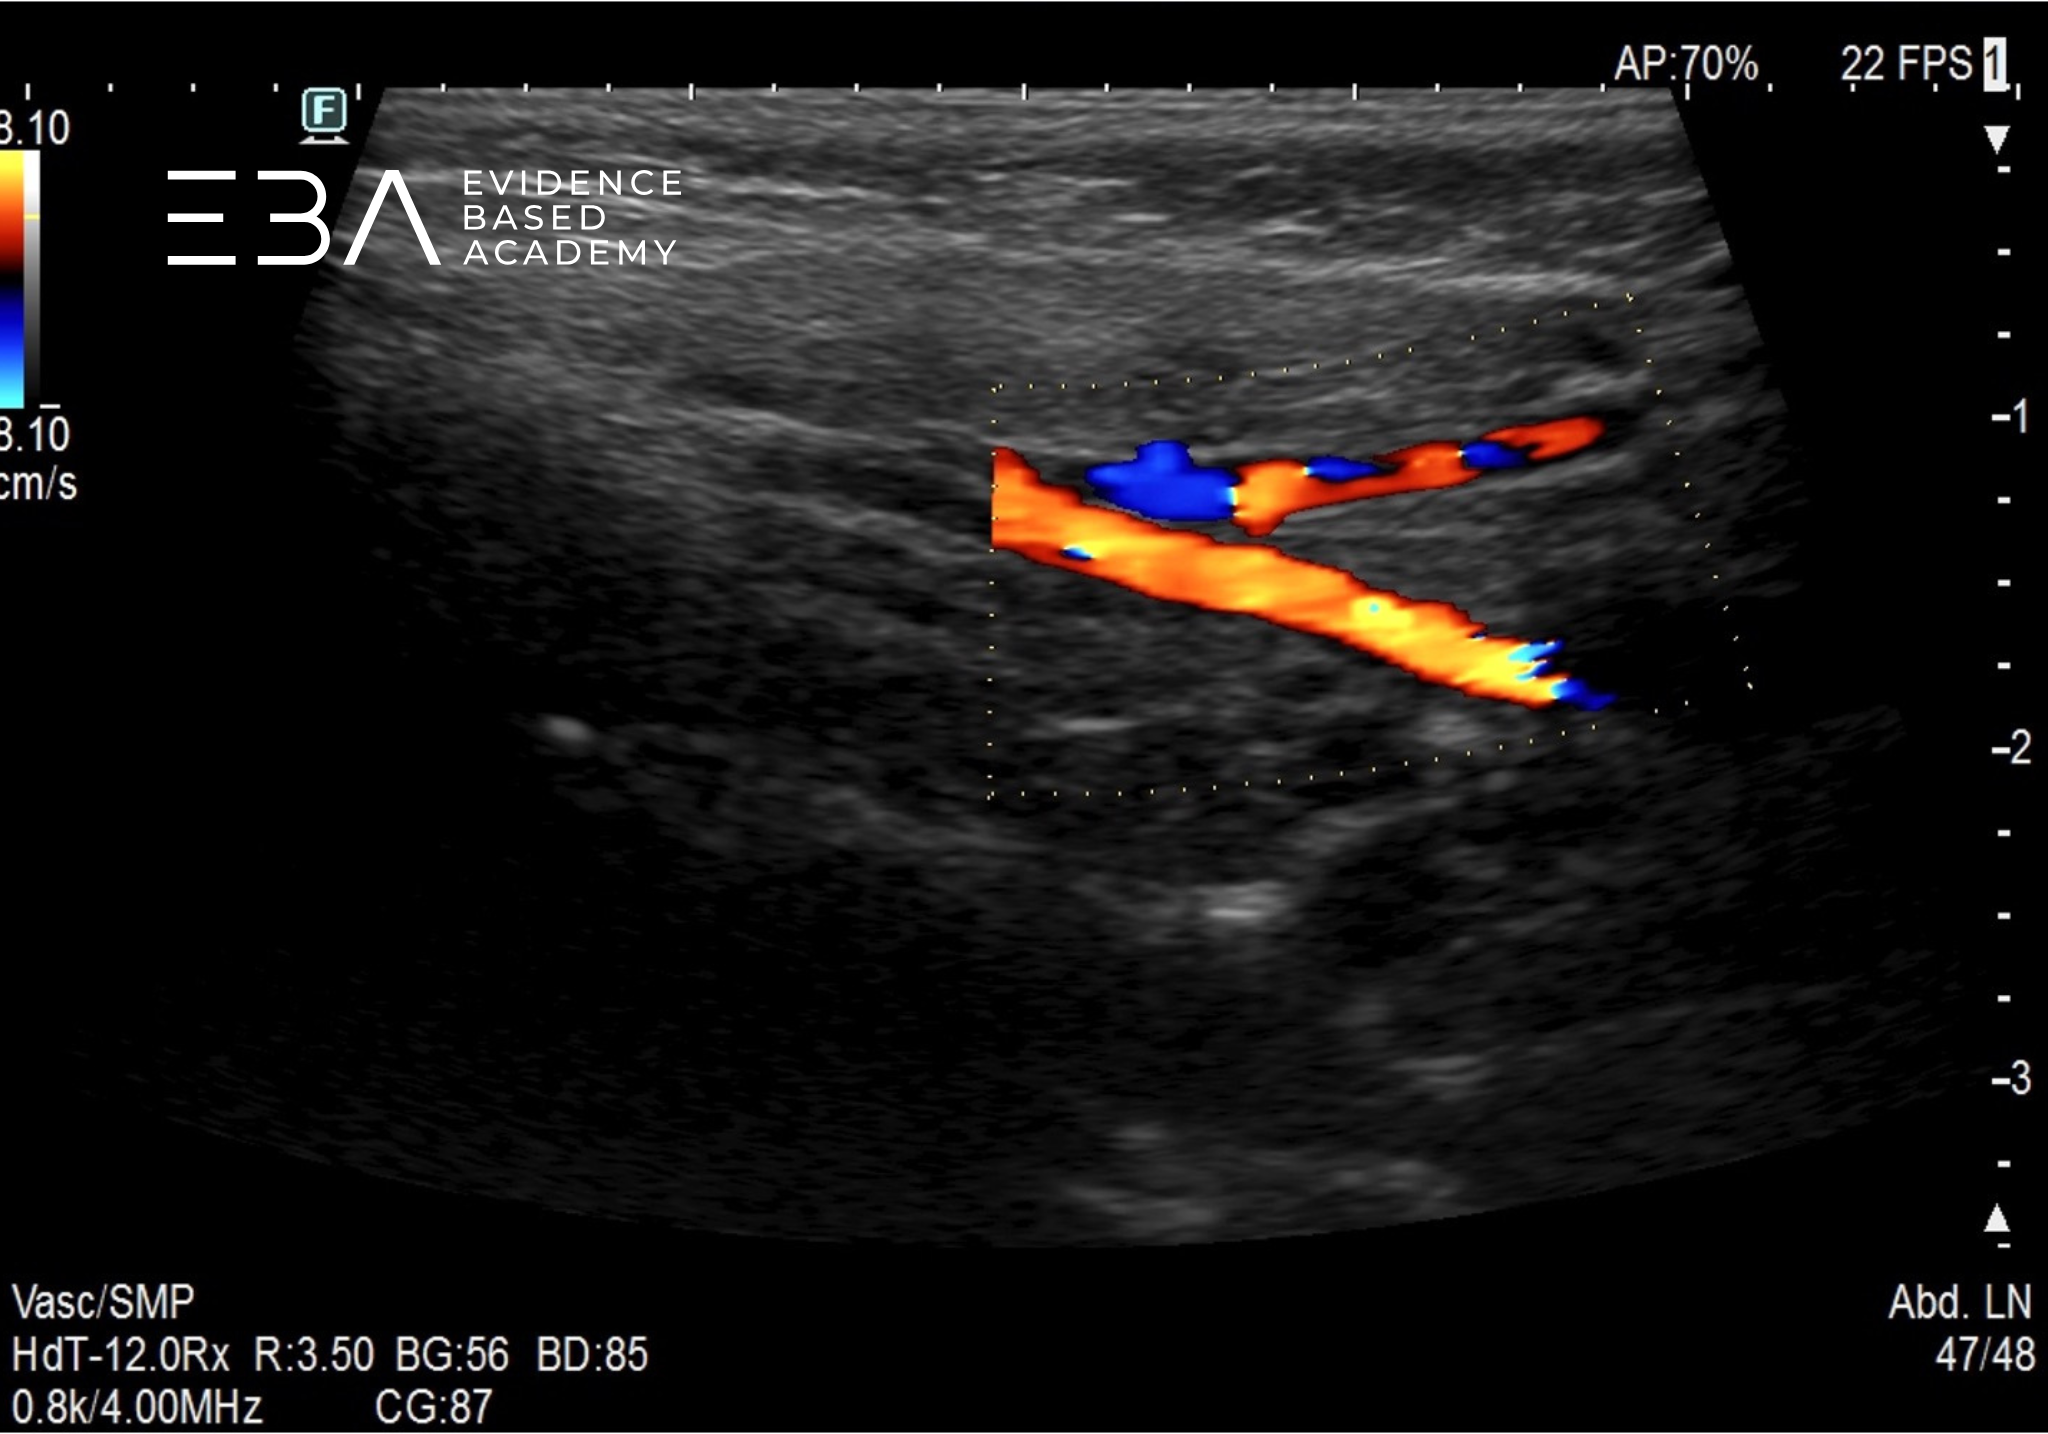

Integralną częścią oceny ślinianek jest ocena węzłów chłonnych szyjnych. O tym, jak ocenić węzły chłonne szyjne u dziecka, możesz posłuchać w tym wykładzie.